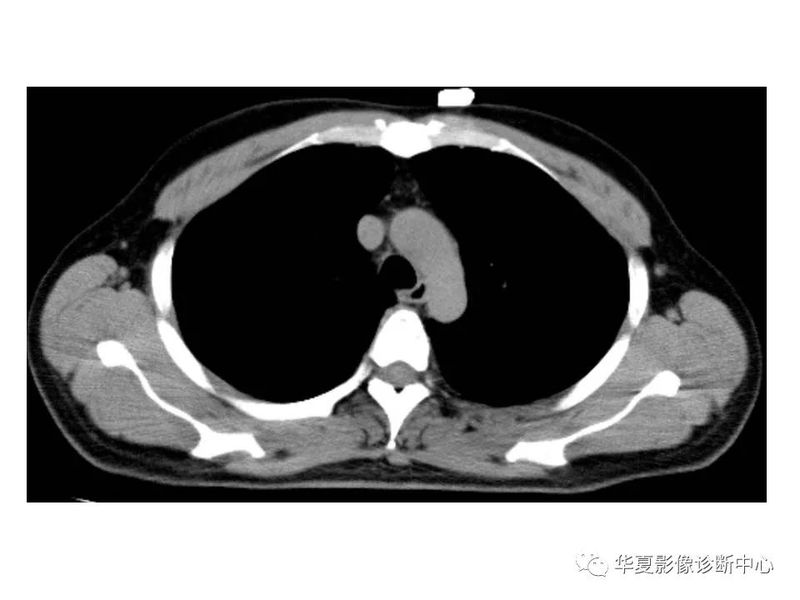

干货 | 汇总胸部CT读片扫盲知识,看懂胸部CT不再难